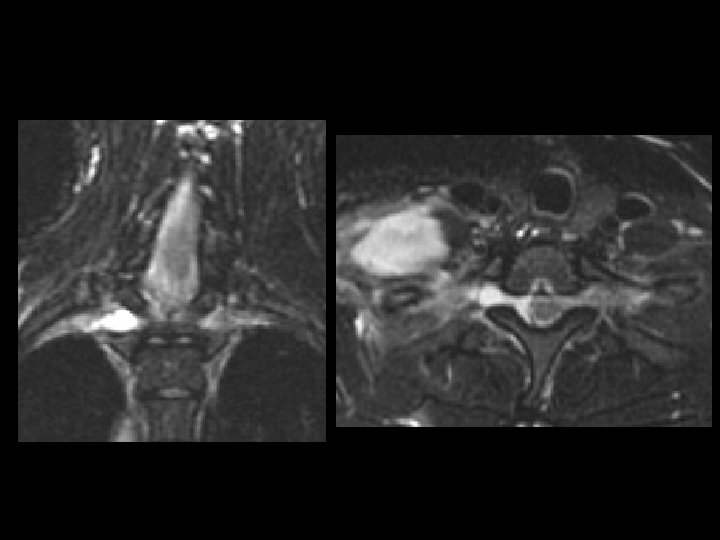

Septic Sacroiliitis • • • Findings: – Low T 1, high T 2 abnormality in the right SI joint Uncommon infection usually due to strep ddx: – Unilateral • Gout • Osteoarthritis – Bilateral & symmetric • Ankylosing spondylitis • Inflammatory Bowel Dz – Bilateral & asymmetric • Psoriatic arthritis • Reiter syndrome • Rheumatoid